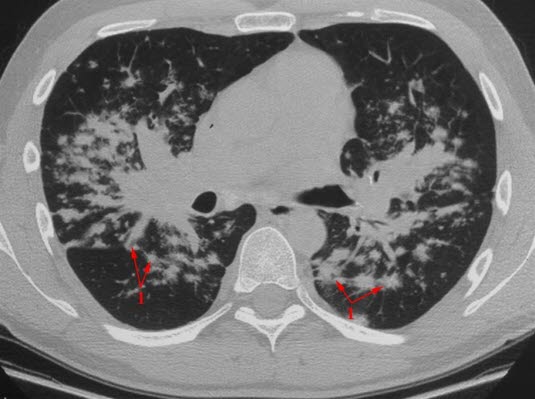

Sarkoidose

HRCT (High resolution CT)

En millimeter tykt CT-snitt

Uregelmessige små knuter (granulomer) med hovedsakelig sentral fordeling